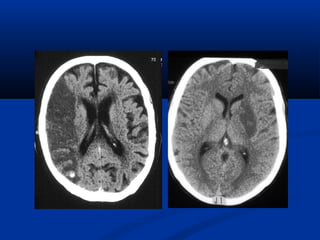

NOÄI SOI AÛOPHEÁ QUAÛN